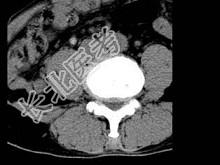

- 单项选择题男,45岁, 腰痛,结合图像, 最可能的诊断是 ( )

A、椎间盘膨出

B、椎间盘突出

C、椎间盘未见异常

D、腰椎骨质增生

E、前纵韧带钙化